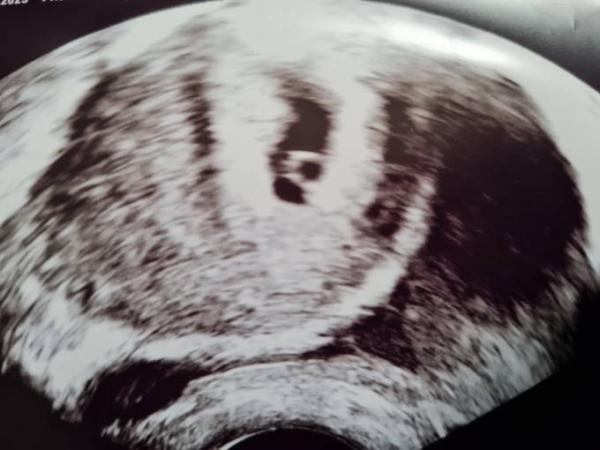

Erster Ultraschall 5+3

Ich hatte heute schon meinen ersten Ultraschall weil ich heute früh nach einer leichten Schmierblutung ziemlich Panik hatte...sieht aber alles gut aus und ich habe so Vaginaltabletten bekommen zur Sicherheit

Herzlichen Glückwunsch! Ist das die Fruchthöhle + Dottersack?

Ja genau, wahrscheinlich hätte man mit einem besseren Ultraschallgerät auch mehr erkannt. Nächste Woche bin ich nochmal bei meinem eigentlichen Arzt (der diese Woche im Urlaub ist) und hoffe auf ein Bild vom Embryo:)